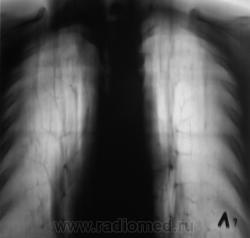

Архива нет. Эта флюорограмма была "первой". Ранее пациент проживал в другом районе.

При расшифровке флюорограмм, пациент "взят на контроль". Произведено стандартное дообследование.

Прямая дорога к фтизиатру. Неясно, что творится в средней доле, создается впечатление инфильтрации и наличия полости. Желательны ТГ ср. доли или хотя-бы прицельный снимок. Да и на правой верхушке поставить однозначно "остатачные явления" я бы не рискнул.

Да складывается впечатление о течении спецпроцесса. А в средней доли или инфильтрация или грудная мышца с соском. Но каков прицел!!! Заметить такую тенюху на верхушке а потом еще и раскрутить! Кстати Валентин Львович, а как на счет рентген нагрузки, как Вы полагаете сколько можно сделать томограмм, а то меня зав. третирует, что я выполняю по 5-6 томограм, причем они меньше Ваших максимум 24х30.

А справа на верхушке то не туберкулома?

да, туберкулома